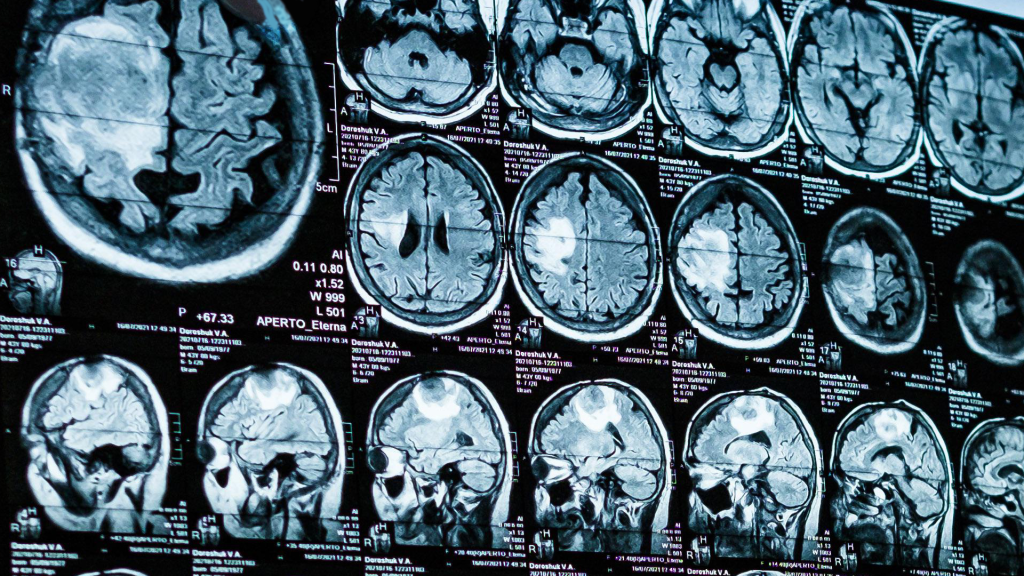

“Hidden Brain Signal” Could Flag Alzheimer’s Years Before Symptoms – FIU Study Points to TSPO as an Early Warning Sign

In‑Depth Report Background: What is TSPO and why focus on it? TSPO (translocator protein, 18 kDa) is a stress‑response protein that sits in glial cell mitochondria. In a healthy brain it’s expressed at low levels; when homeostasis is disrupted, glia—especially microglia—can ramp